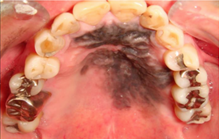

歯の生えている部分の粘膜を歯肉と言い、そこに出来るがんを歯肉がんと言います。

粘膜が赤くなったり、白くなる、表面が凸凹する、潰瘍ができるなどの症状があります。

歯周病でもないのに、歯がぐらぐらする・腫れる、歯を抜いた後、なかなか治らないなどの症状のこともあります。

歯ぐきの表側だけでなく裏側にできることも多いので注意が必要です。